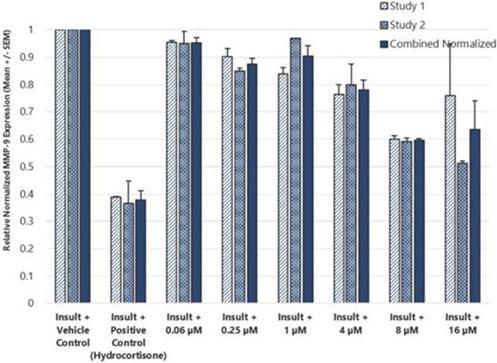

In addition to relief of symptoms, inflammation, pain, and others, we believe INM-755 may impact the underlying disease by enhancing skin integrity in a subset of EB patients. We have completed more than 30 preclinical pharmacology and toxicology studies to investigate the effects of CBN. Several of these nonclinical studies explored the effect on important symptoms such as pain and inflammation. In in vitro pharmacology studies, CBN demonstrated activity in reducing markers of inflammation. CBN upregulated expression of a type of keratin called keratin 15, or “K15”, which might lead to skin strengthening and reduced blister formation in EB simplex, or “EBS”, patients with mutations in another keratin called keratin 14, or “K14”. The anti-inflammatory activity of CBN may be beneficial in healing chronic wounds caused by prolonged inflammation. Following a review of our toxicology studies, the Netherlands National Competent Authority and Ethics Committee approved the initiation of a Phase I clinical study in healthy volunteers. We have safety data with INM-755 cream in 22 healthy adult volunteers from our first Phase I study (755-101-HV) in which subjects had the INM-755 cream applied to their upper backs daily for 14 days. An interim safety analysis of the first 16 subjects was reviewed by the Netherlands National Competent Authority and Ethics Committee and determined to be adequate to allow initiation of the second Phase I study testing INM-755 cream on small wounds. That second study has completed and we now have safety data for INM-755 cream applied to small open wounds daily for 14 days in 8 healthy adult volunteers.

In preclinical pharmacology studies, CBN demonstrated activity as an anti-inflammatory and antinociceptive agent. CBN upregulated expression of keratin 15 (K15), which might lead to skin strengthening and reduced blister formation in EBS patients with keratin 14 (K14) mutations. At the cream concentrations chosen for clinical development, it does not appear to impede wound healing of partial-thickness wounds. Its anti-inflammatory activity may be beneficial in healing chronic wounds caused by prolonged inflammation.